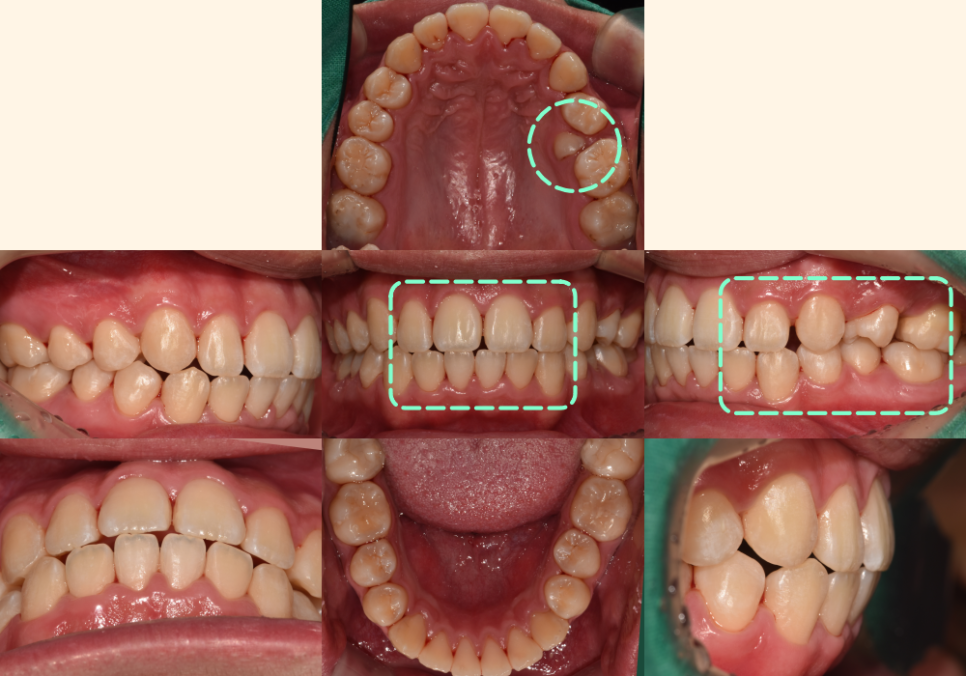

[공간 확보]

22.08.12

매복된 치아를 끌어내기 위한

공간을 만드는 과정입니다.

첫 번째 작은 어금니를 발치하여

필요한 공간을 확보해요.

이 치아는 저작 기능이 상대적으로 낮고,

발치 후 공간을 닫기에도 유리한 위치에 있습니다.

[매복치 견인]

23.02.25

잇몸을 살짝 절개하여 매복된 치아에

교정 장치를 부착하고,

미니스크류나 기타 고정원을 이용해

서서히 정상 위치로 끌어내는 과정이죠.

23.06.23 // 23.11.25

이 과정에서는

이가 올바른 방향으로 나오도록

정기적인 조정과 관찰이 필수입니다.

[사랑니 이동]

24.05.01

손상된 어금니 대신

건강한 사랑니를 앞쪽으로 이동시켜

어금니 역할을 하도록 하는 과정입니다.

이는 임플란트나 브릿지 없이도

자연치만으로

문제를 해결할 수 있습니다.

24.09.05//25.01.10

동시에 절단연 교합과 정중선 문제도

전체적인 치아 이동 과정에서 같이 개선됩니다.

치아들이 올바른 위치로 이동하면서

자연스럽게 교합 관계도 정상화되죠.